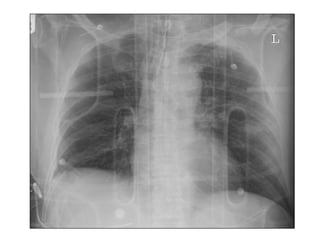

Como se lee una

placa de tórax

Como se leeuna placa de tórax ?????... •?

Traquea y bronquios Espaciospleurales y parénquima Mediastino Diafragma Torax óseo Tejidos blandos Sondas y líneas